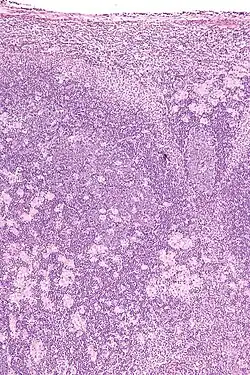

Toxoplasmosis in humans is diagnosed through biological, serological, histological, or molecular methods, or by some combination of the above.[62] Toxoplasmosis can be difficult to distinguish from several other conditions, especially ones that are common in HIV/AIDS and immunocompromised patients, and can cause central nervous system problems and brain lesions.[68] Toxoplasmosis is most commonly mistaken for primary central nervous system lymphoma, both conditions cause lesions in the brain, but in about 50-80% of cases the lesions appearances can be very similar on imaging, and exist in an area of the brain that makes biopsying too risky, however the main difference is lymphoma typically causes a single lesion in the subependymal region, and toxoplasmosis causes multiple lesions scattered through the basal ganglia.[69] Other conditions that can present as toxoplasmosis on a differential diagnosis are metastatic brain lesions, progressive multifocal leukoencephalopathy[70], CNS tuberculosis[71], bacterial or fungal brain abscess, cytomegalovirus (CMV),[72] and herpes simplex encephalitis.[68][73]

Lymph nodes affected by Toxoplasma have characteristic changes, including poorly demarcated reactive germinal centers, clusters of monocytoid B cells, and scattered epithelioid histiocytes.